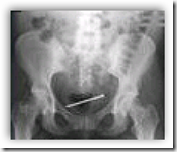

A 35-year-old woman with bipolar disorder was found wandering on a highway screaming and crying, with disorganized speech. She was evaluated in the emergency department, and computed tomography of the head revealed a hypodense area. The patient reported that she had a nail in her uterus. In the context of the presentation, this was deemed to beunlikely. However, before magnetic resonance imaging was performed for further evaluation, radiography of the abdomen showed a large nail, which was localized to the bladder on ultrasonography, and an intrauterine device in the uterus. Surgery was scheduled to remove the nail, but on the morning before surgery, the patient painlessly passed a 10-penny 8.3-cm steel nail while voiding. After resolution of this psychotic episode, the patient revealed that her intention was to place the nail in her uterus as a means of protection against being raped, which had occurred in the recent past. She was subsequently admitted to a psychiatric facility.